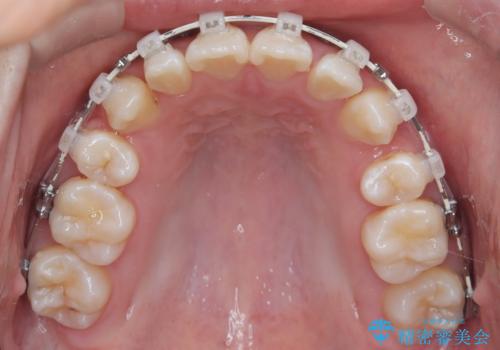

- 前歯のガタガタや正中の不整を改善するために、右上4、左上4、左下4を抜歯し、矯正治療を行いました。この治療により、見た目だけでなく、咬合のバランスも改善され、患者様の口腔内の健康が向上しました。

審美ワイヤー装置は、見た目を重視した矯正治療において非常に有効な選択肢です。患者様のニーズに応じた治療が可能で、美しい歯並びを目指すことができます。